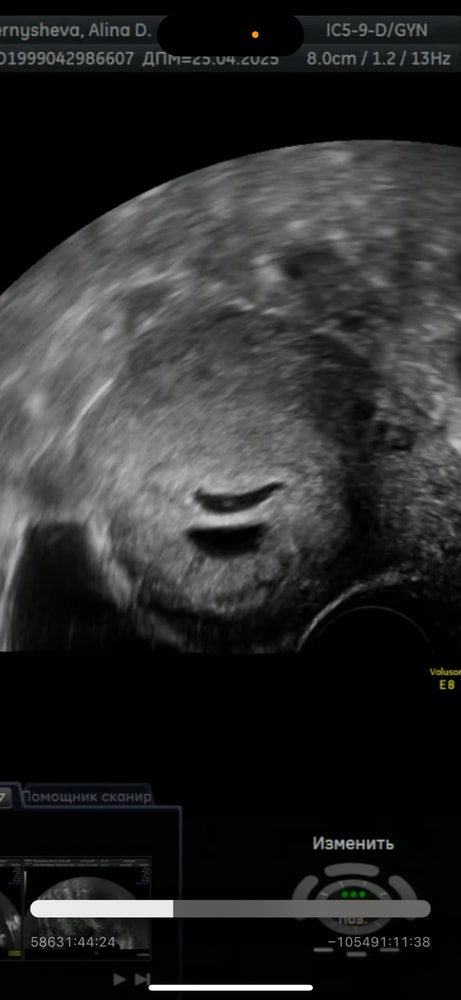

Вчера переделала узи, услышали сердцебиение. Рядом с ПЯ врач увидела полость, сказала, это либо отслойка/гематома, либо второе плодное яйцо, но пустое.

Как вам кажется, что это, гематома, или второе ПЯ?